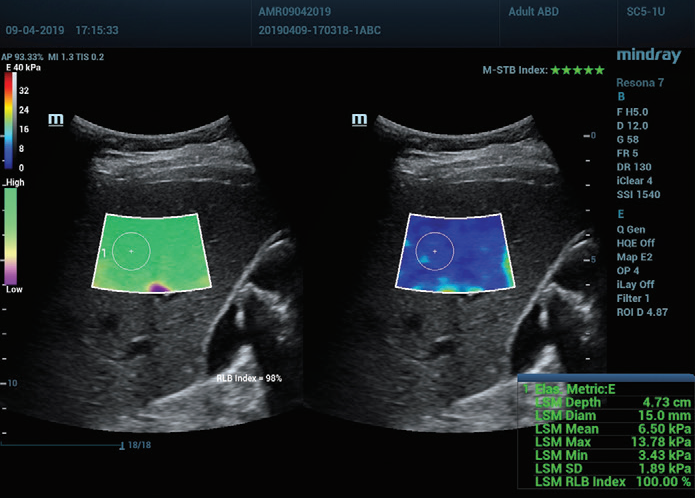

Figure 1 (continuación): (e) Imágenes obtenidas con SWE 2D (STE; Mindray, Shenzhen, China). Se proporcionan dos criterios de calidad: el índice de estabilidad de movimiento (M-STB), que se indica con estrellas (la estabilidad más alta se muestra con cinco estrellas verdes), y el esquema de confiabilidad (RLB), que va de violeta a verde, siendo este último el que indica la confiabilidad más alta. Las estrellas son indicadores de movimiento durante la adquisición. Si hay menos de cuatro estrellas, significa que hay un movimiento considerable durante la adquisición y ese cuadro no se debe usar para la medición de la rigidez hepática.(f) Imágenes obtenidas

Además, la elastografía Sound Touch (STE) de Mindray ofrece potentes factores de calidad o confianza, incluido el índice de estabilidad de movimiento (M-STB), el mapa de confiabilidad (RLB), el índice de confiabilidad (RLB), etc., para las mediciones obtenidas con elastografía de ondas transversales 2D, lo que ayuda a los operadores a confirmar los estándares de adquisición de imágenes.

El índice de M-STB indica la estabilidad del movimiento del tejido producida por la respiración del paciente o la compresión del operador, que ayuda a eliminar la interferencia del movimiento. Se indica mediante estrellas (la estabilidad más alta se muestra con cinco estrellas verdes), una imagen confiable debe tener ≧4 estrellas verdes.

El mapa de RLB indica la confiabilidad de las imágenes de STE, que va de violeta a verde, siendo este último el que indica la confiabilidad más alta. Si el índice de RLB es ≧90 %, la imagen es confiable.